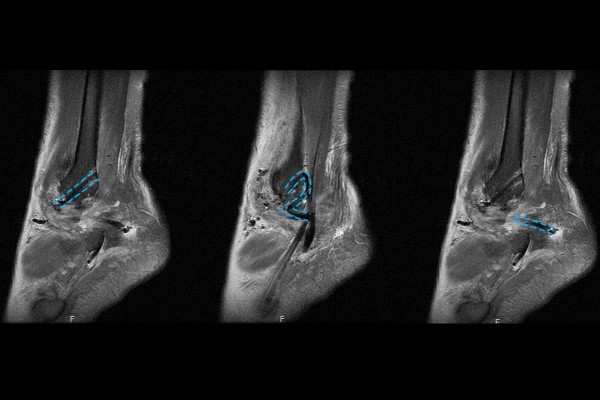

환자분의 병력을 들은 후 신체 검진을 진행하였고, 발목을 흔들어봤을 때 앞으로 빠지는 발목 불안정증이 확인되었습니다. 정확한 발목 인대 상태를 확인하기위해 MRI 검사를 진행하였고, MRI 검사 결과, 인대가 붙는 부분에서 거의 보이지 않고, 전체적으로 질이 떨어져 있는 상태가 확인되어 발목인대파열(재재파열)(Lt. ankle ATFL re-tear)을 진단하였습니다.

수술 후 MRI를 확인해보면 뼈에서 앞으로 가는 전거비인대와 돌아서 뒤로 연결되는 종비인대가 잘 재건,이식된 것을 확인할 수 있습니다.